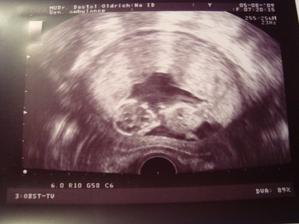

............13.8.09 máme úspěšně za sebou sreening v I trimestru s výsledkem negativní 🙂)) a měříme od hlavičky po kostrč 7,55cm,rovnou nás objednal na další sreening na 1.10.09 .